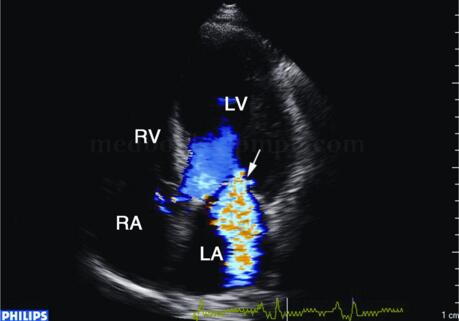

彩色和脉冲多普勒可探及多瓣口反流信号(图2‐1‐181)。连续多普勒测量舒张期二尖瓣血流E峰明显升高,A峰明显降低,E/A>2,EDT<140毫秒,提示左室充盈受限。连续多谱勒可探及三尖瓣反流速度加快,提示肺动脉压力升高。

图2‐1‐181 心尖四腔切面显示左室明显增大,彩色和脉冲多普勒探及二尖瓣中度反流信号(箭头)

超声描述 左室下壁、后壁心肌变薄,约5mm,心肌回声增强,运动消失,其余节段心肌向心运动亦不同程度减弱,左心增大,左室略呈球形扩张,左室舒张末期内径63mm,左室泵血功能减低,左室EF32%。二尖瓣环扩张,探及中度二尖瓣反流。

超声诊断 左室下后壁心肌节段变薄、运动消失,其余节段运动减弱,符合缺血性心肌病改变,左室泵血功能减低,二尖瓣中度反流,提示乳头肌功能不全。